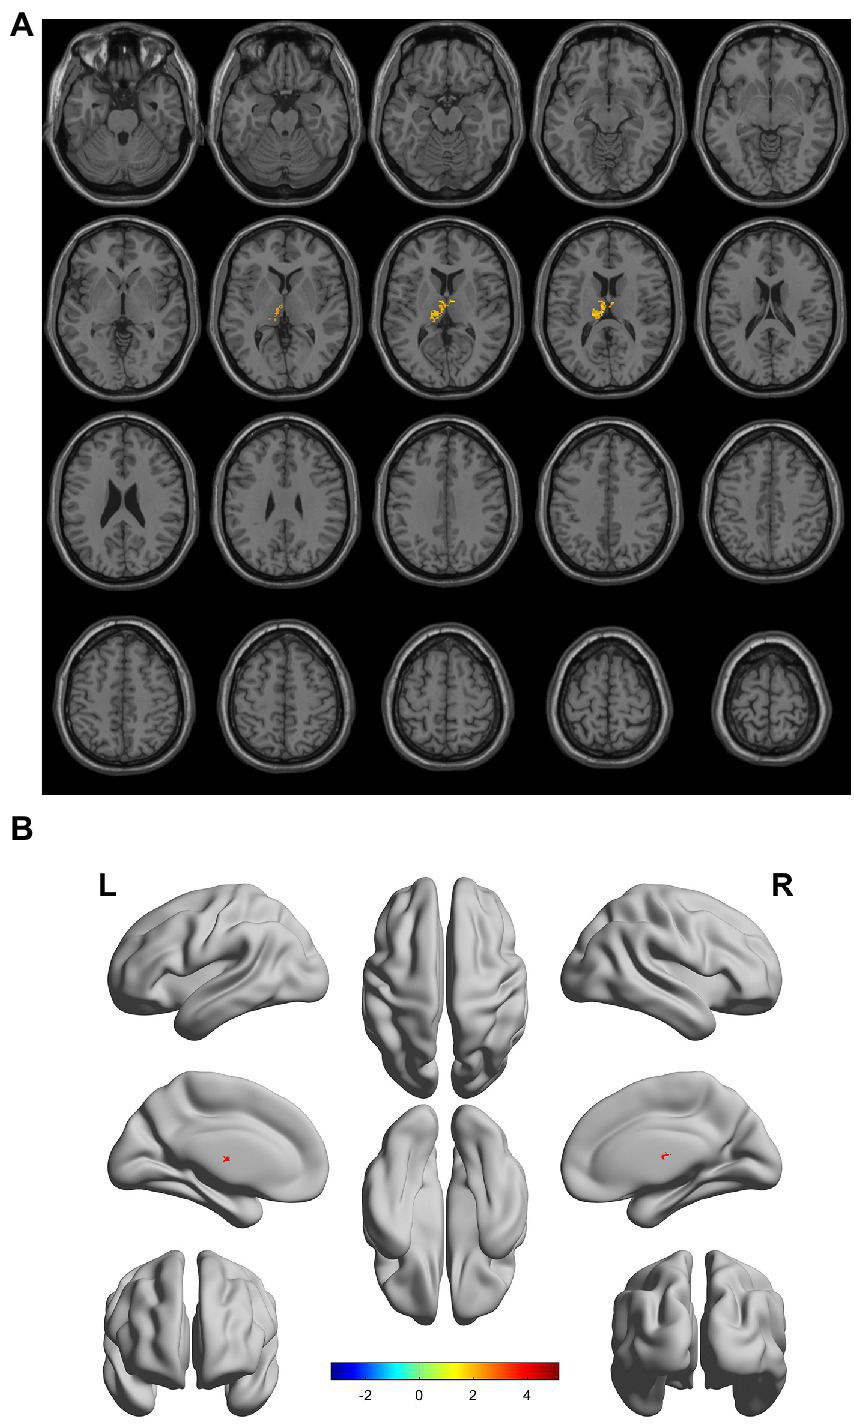

There were gray matter atrophy changes observed in the bilateral orbitofrontal gyrus, right middle temporal gyrus, superior temporal gyrus, and precuneus in the SIVD-VCIND group compared to the NC group (p < 0.05, family-wise error corrected; see Figures 2A,B for detailed data). Compared with the NC group, gray matter atrophy was observed in the left cerebellar region 6, cerebellar crural region 1, bilateral thalamus, right precuneus, and calcarine in the SIVD-VD group (p < 0.05, family-wise error corrected; see Figures 3A,B for detailed data). Compared with the SIVD-NCI group, gray matter atrophy changes were observed in the right cerebellar region 6, cerebellar regions 4–5, left cerebellar region 6, precuneus, thalamus, bilateral median cingulate, and paracingulate gyri in the SIVD-VD group (p < 0.05, family-wise error corrected; see Figures 4A,B for detailed data). Compared with the SIVD-VCIND group, gray matter atrophy changes were observed in the bilateral thalamus in the SIVD-VD group (p < 0.05, family-wise error corrected; see Figures 5A,B for detailed data; Table 4).

Figure 5

(A, B) Compared with the subcortical ischemic vascular disease (SIVD)-vascular cognitive impairment no dementia group, the distribution of gray matter atrophy changed in the SIVD-vascular dementia group. Orange-yellow shows the areas of difference.